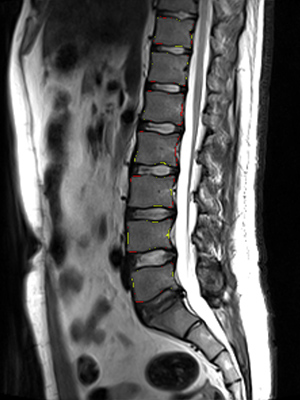

We trained and evaluated the method with five sets of CT and MR scans that visualize the spine. Reference segmentation masks for four of these datasets are publicly available, which allowed for a comparison with other publications that used the same data. Examples of images from the datasets are shown in Figure 3.

The lumbar spine MR dataset consists of 23 T2-weighted turbo spine echo MR images acquired at 1.5T in sagittal orientation (Chu et al., 2015). The scans have a resolution of . Manual reference segmentations are available for 7 vertebrae (T11-L5) in all scans. These reference segmentations contain only the vertebral bodies, not the entire vertebrae.

Similar performance was achieved for vertebra segmentation in various CT datasets with an average Dice score of and for vertebral body segmentation in an MR dataset with an average Dice score of . Surface distances were lower on CT images compared to MR images ( vs. ), however, there were also fewer training scans available in the MR dataset. Figure 4 illustrates the magnitude of differences of the automatic segmentations from the ground truth segmentations.

(c) Lumbar spine MR